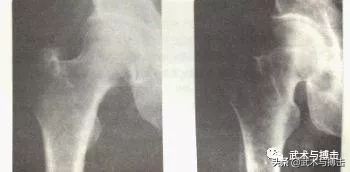

看看马先生的开胯X光图片,两边的股骨似乎延伸开来了,也变得很坚实。事实上,这就是虚拟的锁骨,目的就是平衡上半身的间距,形成如四肢爬行动物一样的四方形状态,这是第一个身形原则。而当你看看不开胯太极拳,他们的胯部的间距空间是呈现倒反的V字的,而开跨太极拳则是平行的H字的。

--左为马岳梁先生开胯x光图片